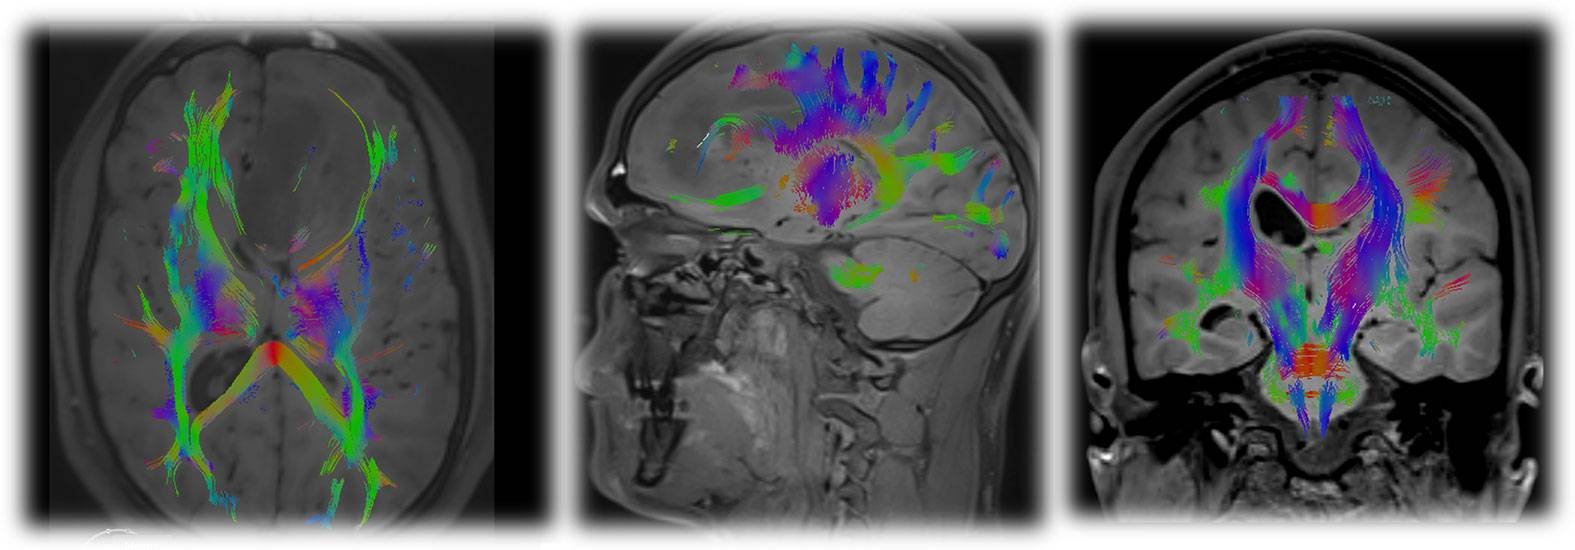

A 5-year-old male child presented with complaints of recurrent generalized tonic–clonic seizures and right-sided weakness ,predominantly involving the lower limb along with anger outbursts and abnormal behaviour.